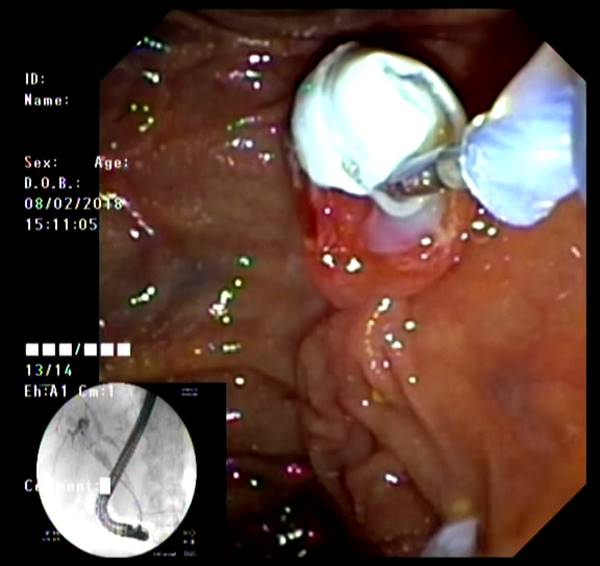

Представлены клинические наблюдения редкого осложнения эхинококкоза печени – прорыва эхинококковой кисты в желчные протоки. Осложнение стало причиной обструкции желчных протоков, механической желтухи и холангита. Освещены этапы диагностики, роль УЗИ в выявлении осложнений эхинококкоза печени, рассмотрены способы минимально инвазивного лечения с применением эндоскопических и чрескожных технологий под контролем лучевых методов.